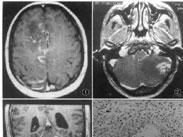

• 東方馬型腦炎

628健康網為您分享有關東方馬型腦炎的癥狀,東方馬型腦炎的治療方法,東方馬型腦炎的預防知識,東方馬型腦炎的癥狀圖片,東...